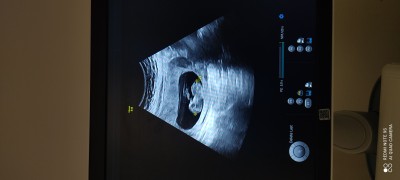

11+5 cinsiyet tahmini yaparmisiniz

image